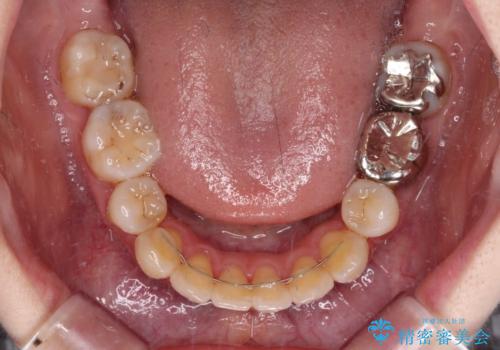

- ハーフリンガル

裏側矯正特有の抜歯スペースに前後の歯が倒れ込む状態が長く続き、改善に長期間を要しました。